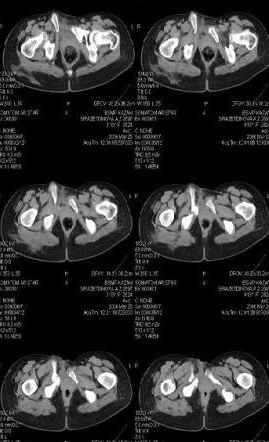

Уважаемые коллеги! Девушка 18л сросшиеся переломы лонных, седалищных костей с обеих сторон, перелом крестца справа,перелом костей голени справа (зио), 3 мес после травмы, АВФ снят с таза. Патологической подвижности нет. Стоит самостоятельно, ходит с костылями, поскольку 3 месяца практически не ходила. Беспокоит выступание лонной кости в области лобка, хотя объективно грубого косметического дефекта нет. На кт разворот лонной кости в сагиттальную плоскость. Вопрос: стоит ли добиватьсяполной репозиции или же достаточно произвести остеотомию верхушки выступающего отломка?

Предварительный диагноз- посттравматическая вертикальная нестабильная деформация таза II степени, неправильно срастающийся перелом боковой

массы крестца справа, правой лонной и седалищной костей, застарелый разрыв лонного сочленения.

Для уточнения диагноза ниеобходимы обзорные рентгенограммы таза (прямая и inlet), Кт срезы на уровне переломов для определения степени сращения и решения вопроса о методе оперативного восстановления анатомии (делать ли остеотомию, низводить ли задние отделы), ни о какой "остеотомии выступающих отломков" тем более у девочки 18 лет речи быть не может.

Предоставляю срезы. Если пациентку функционально ничего не беспокоит, стоит ли навязывать ей лечение.